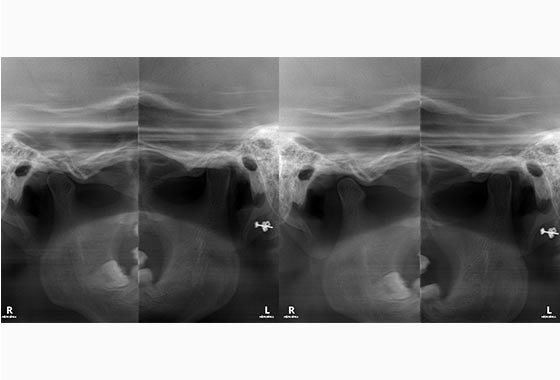

턱관절 질환이란?

턱관절 질환은 대부분 디스크 형태 이상 혹은 위치 이상으로 발생되며, 심한 경우 점차 관절이 닳아 입을 벌리거나 다물지 못하는 상태까지 이르게 되는 질환입니다.

동탄주치과에서는 약물치료, 보톡스, 턱관절 스플린트 등을 통하여 턱관절장애를 치료하고 있습니다.